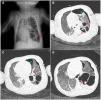

A) Radiografía de tórax (proyección anteroposterior en decúbito): se observan múltiples cavidades áreas en LII en la misma localización que los hallazgos ecográficos compatibles con neumatoceles (flechas, color rojo). B-D) TAC torácico con contraste. Ventana pulmonar: múltiples lesiones quísticas que afectan a la práctica totalidad del lóbulo inferior izquierdo y diámetro de hasta 5cm compatibles con cavidades postinfecciosas (flechas, color rojo). LSI íntegro. Neumotórax izquierdo con tubo torácico de drenaje (signos ×, color verde).